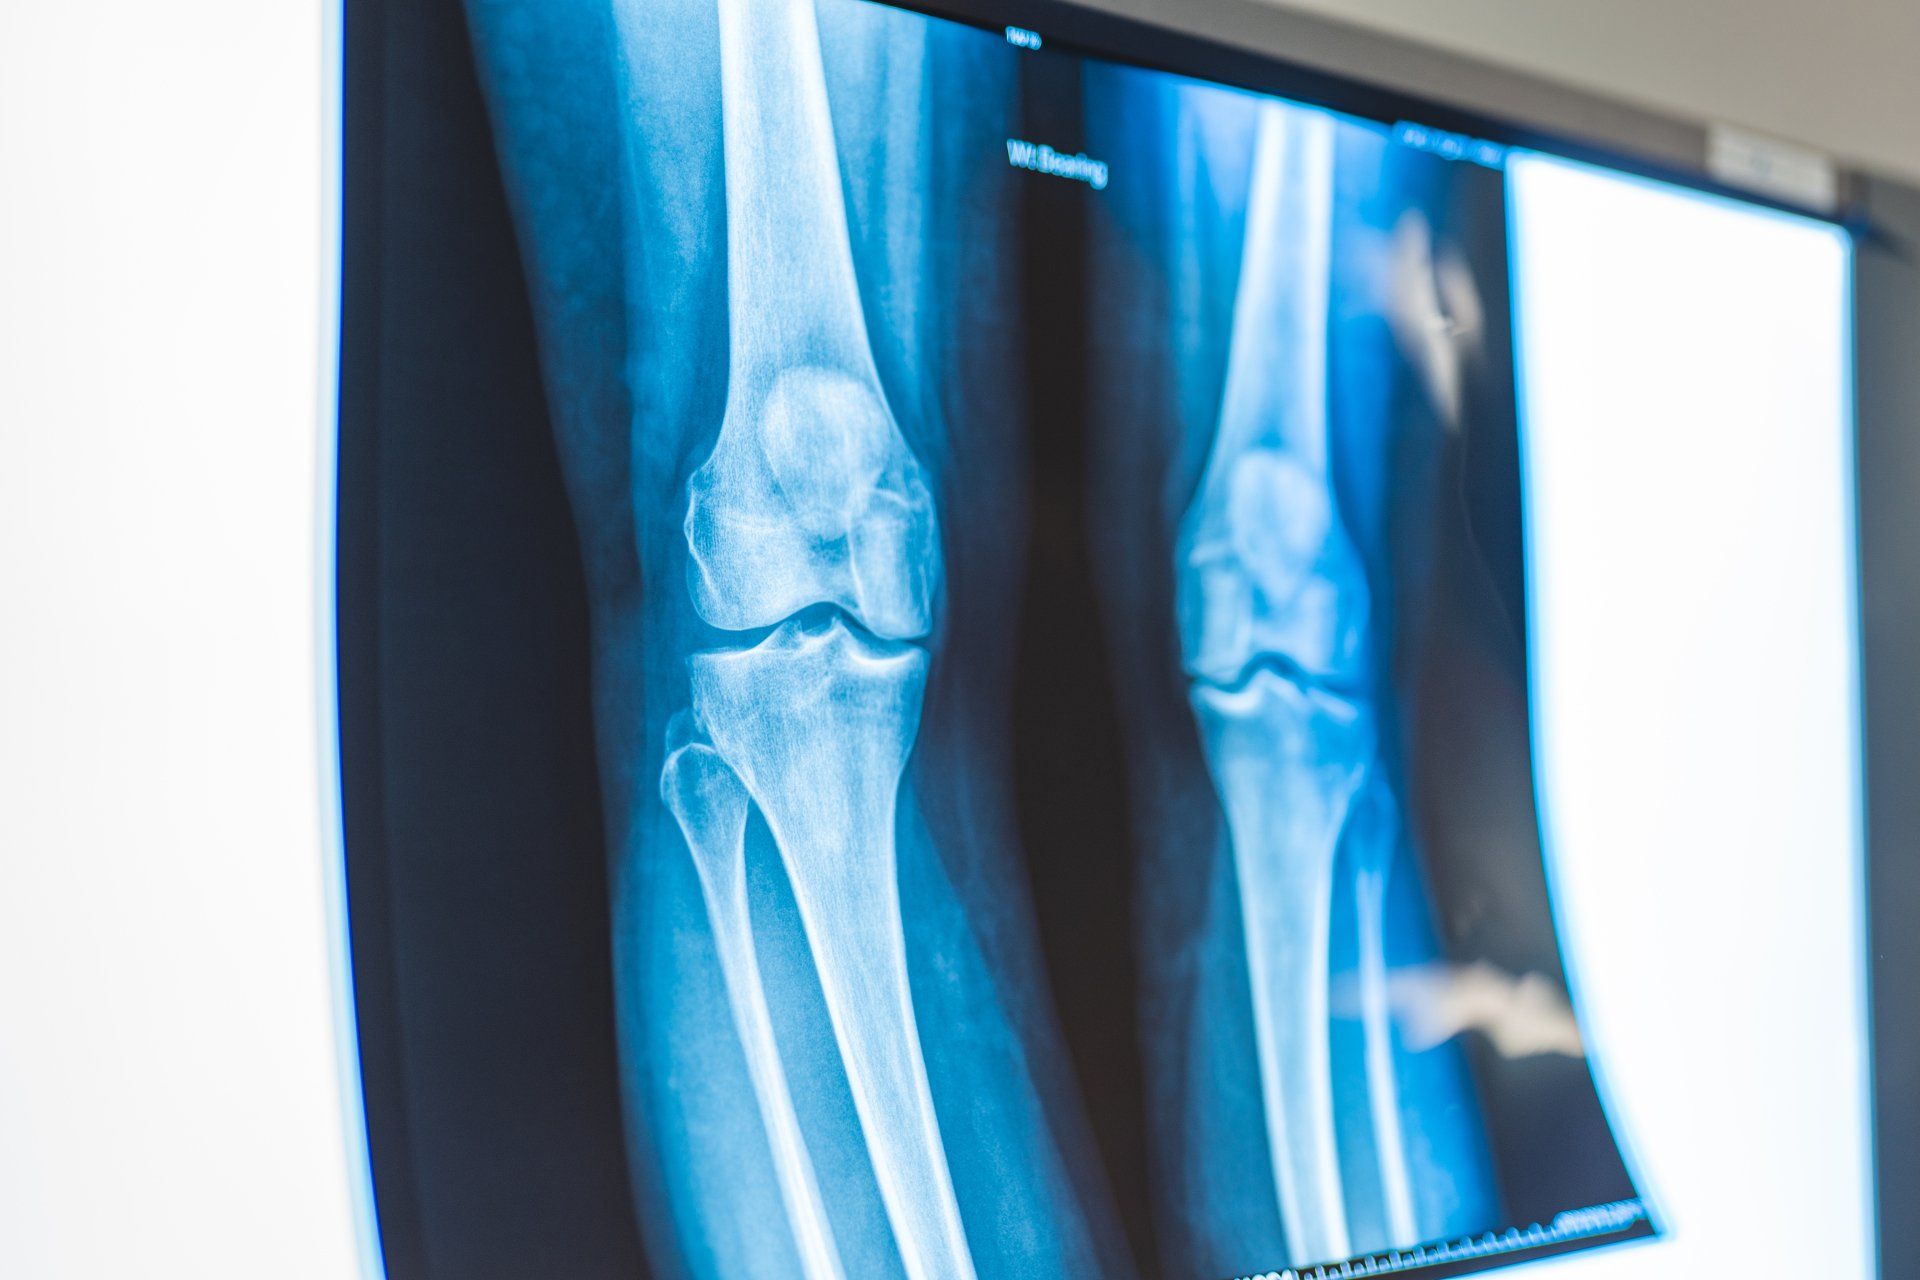

Orthopaedic Surgeries and Services

The services offered by the surgeons at Orthopaedics Toowoomba cover almost the entire spectrum of orthopaedic care. Here you will find summaries of some of the most common conditions treated. Not all procedures that our surgeons perform appear here, but a broad introduction to our field of work is contained in these pages. If you need further information regarding any procedure please discuss it with your surgeon.